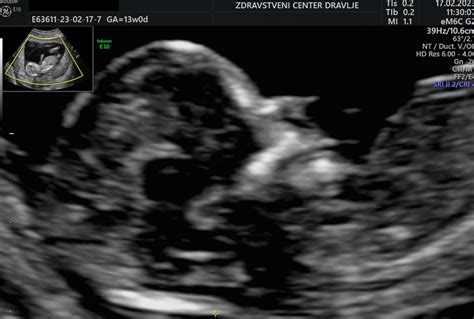

Nuhalna svetlina je v bistvu tekočina, ki se nabere v podkožju v zatilnem delu vratu ploda. Na ultrazvočni sliki se to območje zaradi prisotnosti tekočine prikaže kot svetlejše od okoliških tkiv, od tod tudi poimenovanje "svetlina". Ta pojav je normalen del razvoja ploda v določenem obdobju nosečnosti. Med 11. in 14. tednom nosečnosti se limfni sistem in ledvice ploda še razvijajo, kar lahko povzroči začasno nabiranje tekočine v tem predelu, saj se tekočina še ne more normalno odvajati. Ko se limfni sistem popolnoma razvije, običajno izgine.

Preiskava nuhalne svetline je natančno izvedljiva le v specifičnem časovnem okviru, ki je med 11. tednom nosečnosti (približno 11 tednov in 3 dni) in najkasneje do 13. tedna nosečnosti (približno 13 tednov in 6 dni). V tem obdobju je dolžina ploda ( CRL - Crown-Rump Length) običajno med 45 mm in 84 mm. Izven tega okna lahko natančnost meritve upade.

Med samim ultrazvočnim pregledom, poleg meritve debeline nuhalne svetline, izvajalec sistemaatično pregleda tudi druge ključne parametre ploda v prvem trimesečju. To vključuje merjenje velikosti ploda, srčnega utripa, preverjanje prisotnosti nosne kosti, oceno oblike glavice in možganskih struktur, pregled srca, želodčka in mehurja, preverjanje, ali je trebušček v celoti prekrit s kožo, štetje dolgih kosti na okončinah ter pregled hrbtenice. V določenih primerih je mogoče z manjšo stopnjo zanesljivosti napovedati tudi spol otroka, vendar natančna ugotovitev spola v tej fazi nosečnosti še ni mogoča, saj zunanje spolovilo še ni dokončno oblikovano.